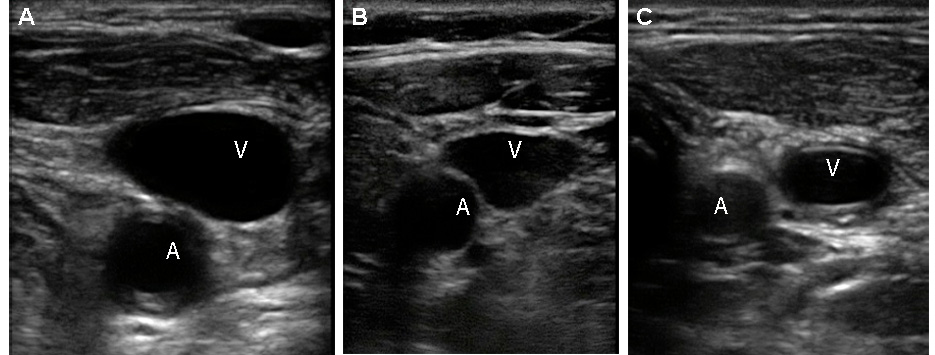

Figura 3.

Ejemplos de diferentes magnitudes de solapamiento. A. Anterior: Las cubiertas de las venas completamente la arteria. B. Antero-lateral: La vena cubre al 50% de la arteria. C. Lateral: La vena se encuentra lateral a la arteria.

La relación entre los vasos se describió de acuerdo con la proporción de la arteria cubierta por la vena (Fig. 3), de acuerdo a lo reportado por otros autores 9,15,18-22. Se escogió este método de describir las relaciones de las estructuras vasculares, a aquellas que lo hacen relacionando la proporción en grados 10,17 o la magnitud de superposición o separación 23.